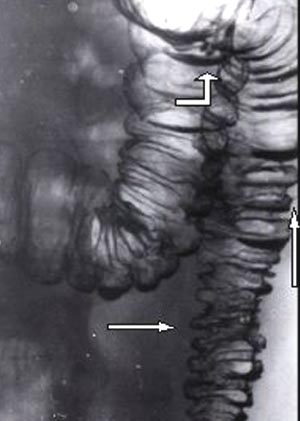

Рис. 2. Сочетание преддивертикулярной стадии в нисходящей кишке (горизонтальная стрелка), стадии интрамуральных дивертикулов (вертикальная стрелка) и полных дивертикулов фигурная стрелка).

Предоставил Дементьев Е.З.

Радиология-практика 2004 2: 48-56